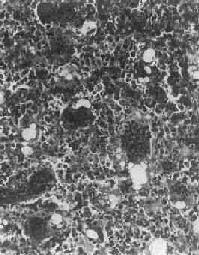

骨巨细胞<a href=瘤(Ⅰ级)"/>

图17-6 骨巨细胞(Ⅰ级)

由大量基质细胞和多核巨细胞两种细胞组成

镜下,肿主要由单核基质细胞及多核巨细胞等两种细胞组成(图17-6),间质血管丰富。基质细胞为梭形、卵圆形或圆形,细胞境界不清楚,常见胞浆突起。细胞核较大,染色质量中等,可具有一个核仁。多核巨细胞常较均匀地散布在基质细胞之间,是为本的特点。多核巨细胞的直径常为30~60μm,核数一般为15~20个,最多可达100个以上,常聚集在细胞的中央。核的形态与单核基质细胞相似。细胞边界不规则,但分界较清楚,胞浆丰富,略呈嗜碱性,有时还可见含大量脂类的泡沫细胞。本间质血管丰富,有多少不等的胶原纤维。肿本身无成骨现象,但有时见有类骨组织及新生骨小梁,常见于纤维组织的周围,可能是一种反应性新骨形成或病理性骨折后形成的骨痂。